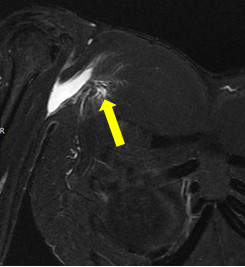

用超音波或核磁共振检查确诊「胸大肌断裂(图/北医附医提供)